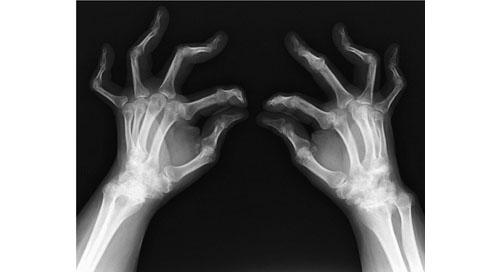

8

理学療法士実地問題 -

第52回 午前

重要度:標準

44歳の女性。関節リウマチ。エックス線写真を示す。身の回りのことはできるが、仕事は行えない。この患者のSteinbrockerの分類はどれか。

1

ステージⅡ、クラスⅡ

2

ステージⅢ、クラスⅢ

3

ステージⅢ、クラスⅣ

4

ステージⅣ、クラスⅢ

5

ステージⅣ、クラスⅣ